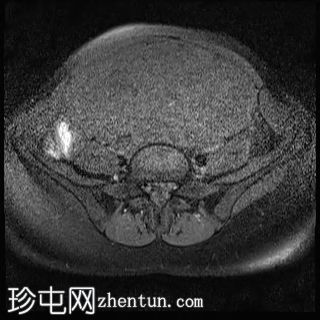

伴有囊性变性的子宫平滑肌瘤

盆腔疼痛,伴有腹部胀满感。

年龄:35岁

性别:女

子宫后壁可见一个边界清晰、体积较大的浆膜下肌瘤,大小约为16.1 x 10.5 x 14.4 cm(宽 x 深 x 高)。

该肌瘤在T1加权像上呈中等信号,在T2加权像上呈低信号,内部区域呈囊性变性。

该肿块导致正常子宫结构严重变形。增强扫描显示轻度不均匀强化,未见弥散受限征象或提示恶性肿瘤的可疑强化。

此外,子宫后壁可见多个小型子宫肌瘤,位于肌壁内和浆膜下,无任何退化征象。

双侧卵巢增大,各有超过10个卵泡,呈珍珠串状排列,周围未见优势卵泡。这些发现符合多囊卵巢的形态学特征。